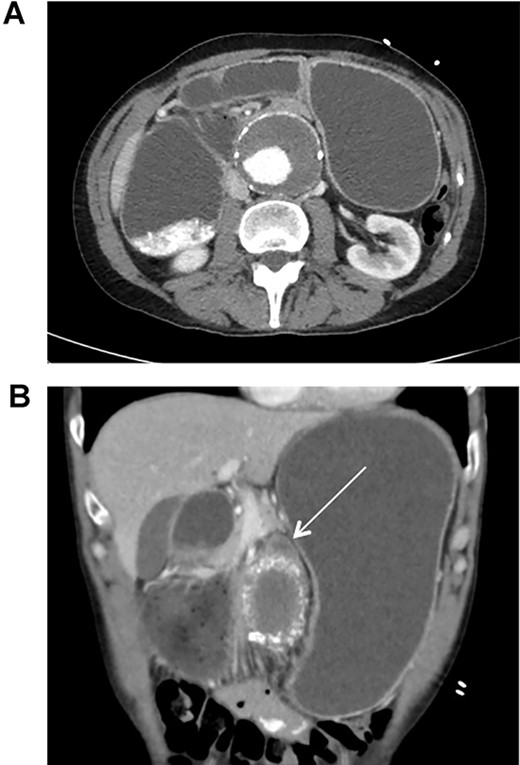

This patient is a 65-year-old male with previously diagnosed AAA who presented to the emergency department due to acute onset of abdominal distension and cramping. He also experienced multiple episodes of nausea, vomiting, and hiccups. On exam, the patient was tachycardic (101 bpm), but normotensive (110/68 mmHg), and in no acute distress. There was a pulsating mass at the epigastrium, without signs of peritonitis. CT scan revealed an infra-renal AAA measuring 6.7 cm in diameter with an interval increase in size since last seen 4 years prior (5.1 cm diameter). The stomach and proximal duodenum were markedly distended with an abrupt change in caliber of the duodenum as it coursed anterior to the AAA.

The patient was initially treated with nasogastric decompression, intravenous fluid resuscitation, and antiplatelet therapy (Aspirin/Plavix). CT Angiogram was then obtained for further evaluation of the patient’s vascular anatomy (Fig. 1). Additionally, the patient underwent esophagogastroduodenoscopy to rule out other etiologies for duodenal obstruction, during which none were found. 48 hours later, he was taken to the operating room for EVAR.

CT scan illustrating duodenal obstruction secondary to external compression of abdominal aortic aneurysm (A); CT scan illustrating transition point of obstructed duodenum as it traverses the abdominal aortic aneurysm (B, arrow).